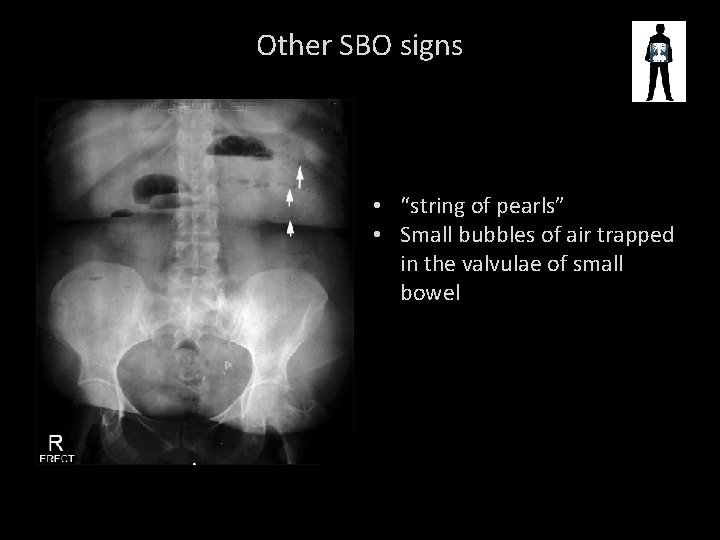

Other SBO signs • “string of pearls” • Small bubbles of air trapped in the valvulae of small bowel